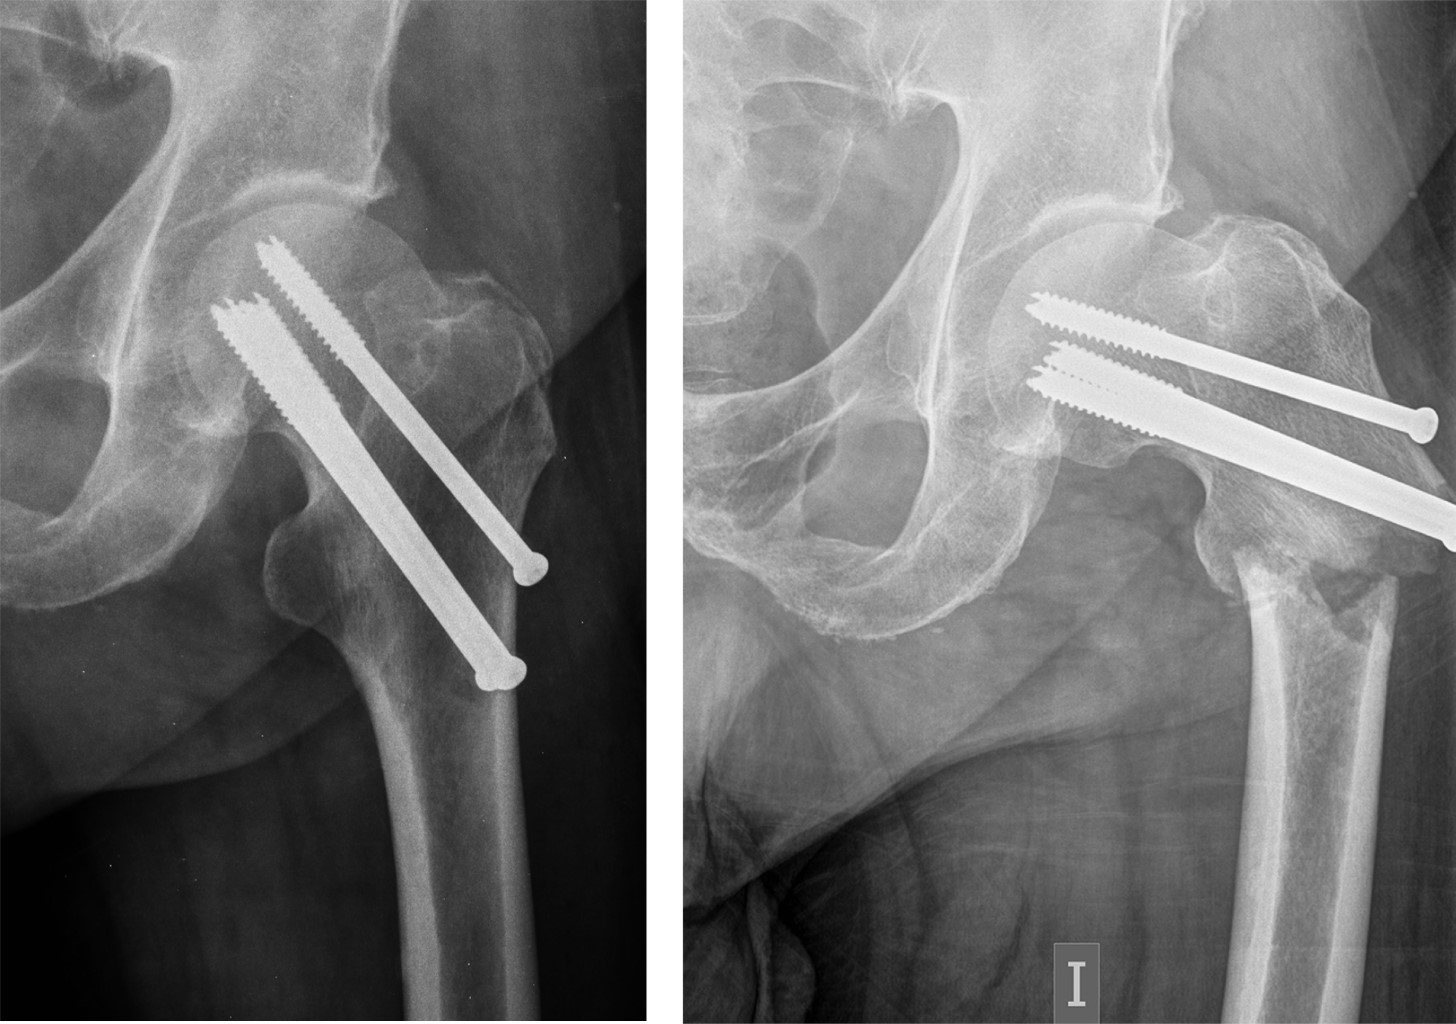

Periosteosynthesis subtrochanteric fractures after fixation of femoral neck fractures with cannulated screws

Introduction: the objective of this study was to analyze the incidence and predisposing factors in subtrochanteric fractures on hips previously treated with cannulated screws after suffering a subcapital fracture, based on eight cases registered in the last 20 years. Material and methods: this is a retrospective observational study on a series of patients with a diagnosis of subtrochanteric hip fracture, who have been treated in recent months for a subcapital fracture of the same hip by osteosynthesis with cannulated screws. The study period was 20 years (2000-2020). Results: of the eight cases, five were women and three were men, with a mean age of 75.12 years (range 59-87 years). In all cases, the subtrochanteric fracture occurred within a year after the first fracture, the time elapsed between the two fractures was four months on average (range 1-9 months). Regarding the disposition of the cannulated screws, most of the 7/8 cases were in the shape of an upper vertex triangle, and only one case was in the shape of an inverted triangle or lower vertex. The entry point into the femoral external cortex was at the level of the lesser trochanter in six cases, and in two cases this entry was distal to the lesser trochanter. Conclusion: in our experience, in the etiology of subtrochanteric fractures, the introduction of screws distal to the lesser trochanter, and the distribution of the screws in a triangular shape are the two main objective predisposing factors.

Figure 1

Figure 2